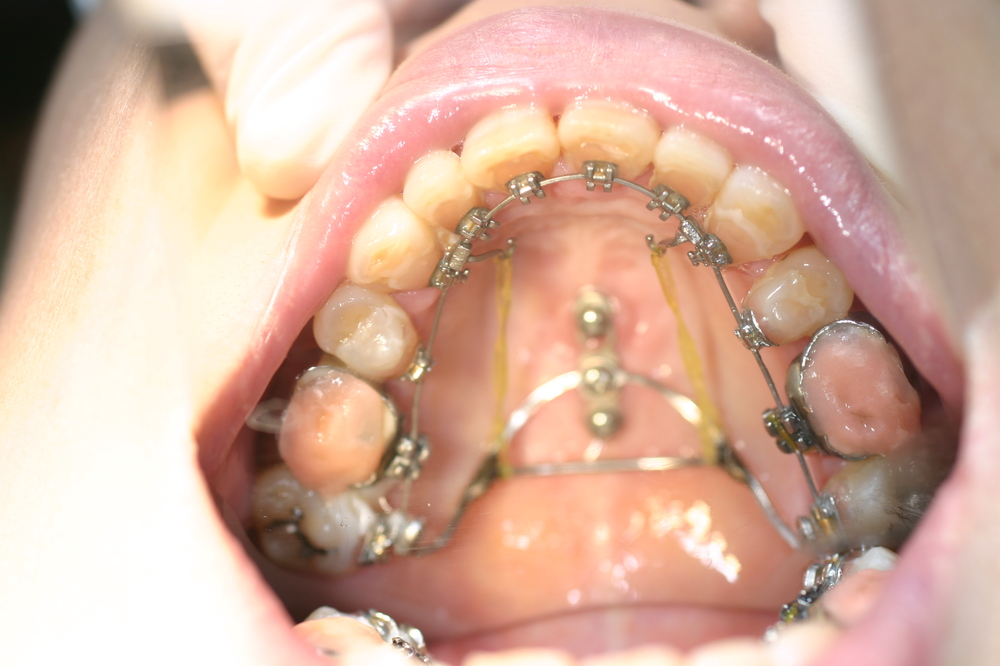

上顎の中央の歯一本が前にとびだしている治療例

上顎の中央の歯一本が前にとびだしている症例です。これだけ前に出ていると、歯を抜いて並べていくか、何本かの歯を削らないときれいに並べられません。

このケースは、上の顎に矯正用のミニスクリュー{矯正用ミニインプラント}を入れて、歯を抜かず、削りもしないで、しかも上顎だけの矯正で治した症例です。

矯正用インプラントを使うことによって歯並び全体を後方に動かすことができるようになったため、このような治療ができるようになりました。

年齢 20代

治療期間 8ヶ月

治療費用 800,000円

治療のリスク 特になし